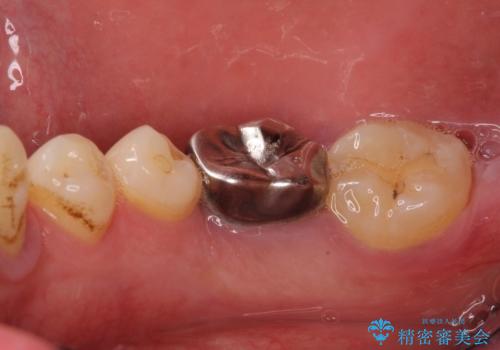

- 前歯や奥歯の虫歯を放置しており、それらの治療を契機に真っ白な歯にしたいとのことで来院された患者様です。

咬み合わせを改善するに当たって、抜歯しなければならない歯や歯列の改善が必要な箇所があったため、矯正治療やインプラント治療から始めていくこととしました。

不自然なくらい真っ白にしたいとのことでしたので、透明感のないフルジルコニアクラウンを用いて補綴することとしました。